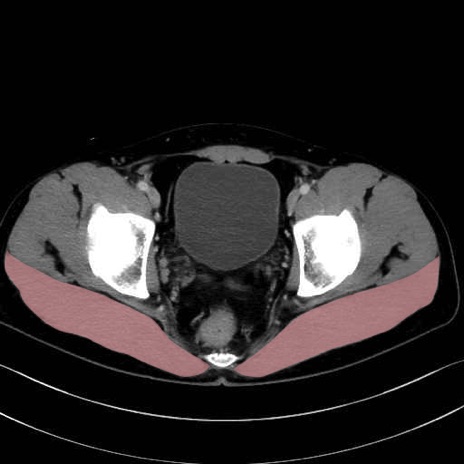

大殿筋 (Gluteus maximus)